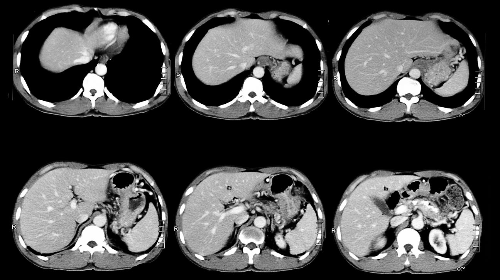

3.CT(전산화 단층촬영)

흉부 CT 촬영은 흉부 엑스레이보다 폐암을 발견할 수 있는 확률이 높고 이로 인해 폐암을 조기 발견하여 사망률은 낮출 수 있습니다. 저선량 CT는 방사선 조사량을 기존 CT에 비해 현저하게 줄이는 검사 방법으로 방사선에 노출되는 위험을 줄일 수 있습니다. 이 검사 방법은 해상도는 저선량이라서 기존 CT에 비하여 감소하지만 병변 유무를 관찰하는 데는 충분하며 간편한 검사입니다. X-ray에서 발견이 어려운 초기 폐암의 경우 흉부 CT 촬영을 통해 조기에 발견할 수 있습니다.